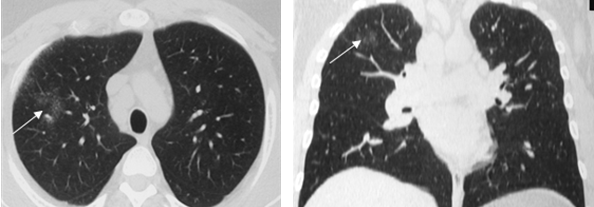

Симптом «матового стекла» (36%) визуализировался в виде небольших, ограниченных участков снижения прозрачности лёгочной ткани (рис. 2).

Рис. 2. РК-томограммы (режим лёгочного окна) пациента Г., 28 лет, с саркоидозом легких и ВГЛУ. Стрелкой указаны участки «матового стекла»

На ранних стадиях заболевания симптом «матового стекла» мог быть единственным, либо сочетаться с увеличением ВГЛУ.